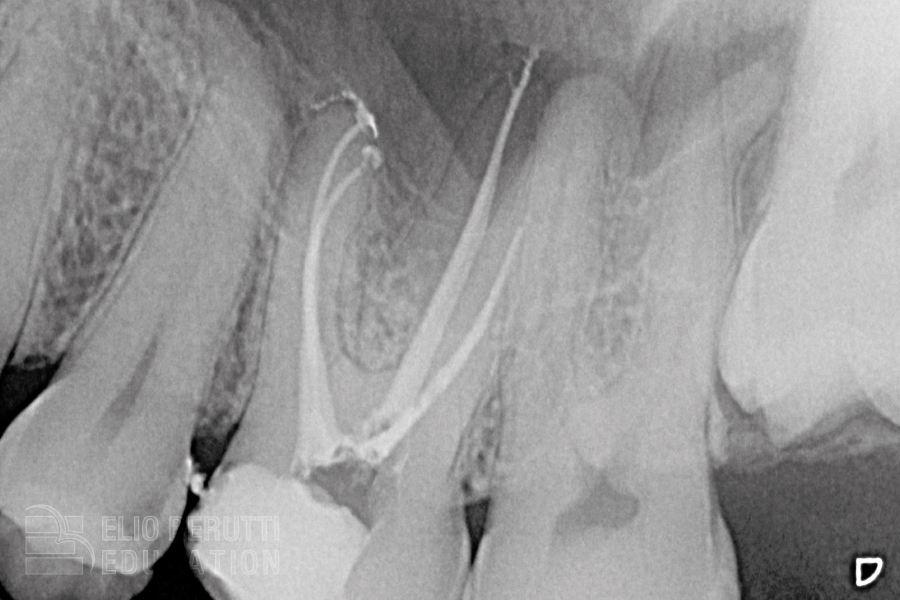

Posto a questo punto che la lunghezza di lavoro è ormai universalmente riconosciuta essere al termine del canale cioè quella rilevata con il localizzatore elettronico del forame (Y.L. Ng 2007- 2008, M.P.J. Gordon 2004, O. Pommer 2002, Mc Donald 1999) dobbiamo chiederci:

⁃ quale è l’ampiezza minima del forame apicale per garantire un corretto flusso degli irriganti sino al forame apicale?

⁃ quale è la conicità minima della sagomatura finale necessaria per garantire un corretto flusso degli irriganti sino al forame apicale ed una semplice otturazione 3D?

La maggioranza dei canali (più del 90%) sono inizialmente sondabili con una lima 10 (0.010 mm) in questi casi la letteratura dimostra che è sufficiente raggiungere il forame apicale con uno strumento endodontico con un punta 25 o 30 (0,025, 0,030 mm) al fine di raggiungere un buon flusso degli irriganti sino al forame apicale. Allargare ulteriormente il forame è quindi ininfluente ai fini della detersione e pericoloso in termini meccanici (L.G. Coldero 2002, A. Khademi 2006, F. Paqué 2009, C. Boutsioukis 2010, A. El Ayouti 2011, A. Aminoshariae 2015, G. Plotino 2019, O.Y.S. Lee 2019).

⁃ Il nostro obiettivo è raggiungere una detersione 3D ed una otturazione 3D mediante una sagomatura mini-invasiva,

⁃ è sufficiente raggiungere il forame apicale con strumento endodontico con punta 25 o 30 (0,025, 0,030 mm) al fine di raggiungere un buon flusso degli irriganti sino al forame apicale,

⁃ la conicità finale .05 si è dimostrata idonea al fine del raggiungimento degli obiettivi necessari per ottenere una terapia di successo di semplice esecuzione alla portata quindi sia del dentista generico che dello specialista.